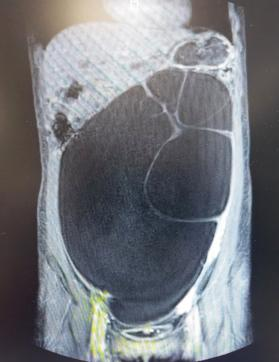

12岁患者术前核磁图片,包块上界位于脐与剑突之间。

巨大包块使得腹部膨隆。